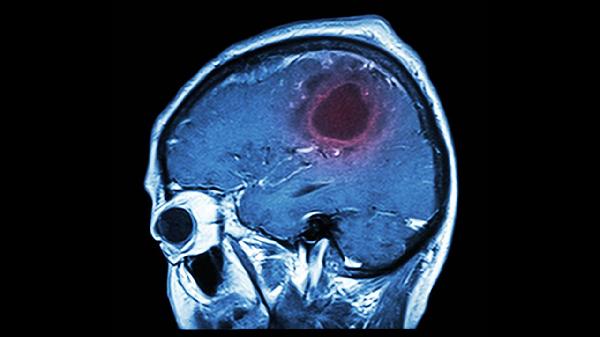

4、意识障碍

大面积小脑梗死可能压迫脑干网状结构,引起嗜睡、昏迷等意识改变。伴随瞳孔不等大或呼吸节律异常时提示脑疝风险,需紧急行去骨瓣减压术。监测颅内压可使用甘露醇注射液降低脑水肿。